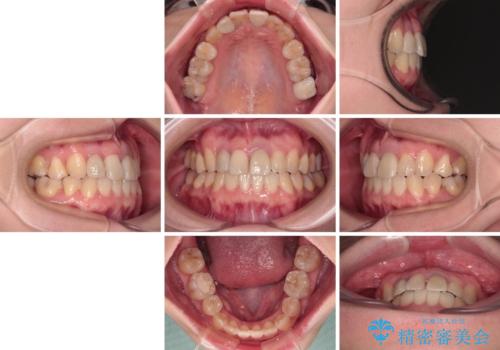

虫歯治療ついでに歯並びの後戻りを改善 インビザラインによる矯正治療

後戻りは軽度であり、インビザラインにて歯列を整え、その後にオールセラミッククラウンにて補綴治療を行うこととしました。

ご家庭やお仕事の都合で通院が途絶えた時期があり、治療は長期間となりましたが、無事に終えることができました。